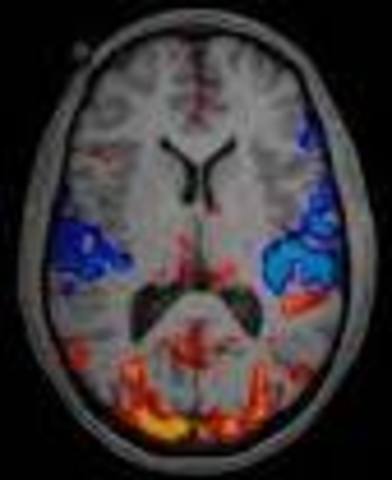

MRI was introduced clinically, and during the 1980s a veritable explosion of technical refinements and diagnostic MR applications took place. Scientists soon learned that the large blood flow changes measured by PET could also be imaged by the correct type of MRI. Functional magnetic resonance imaging (fMRI) was born, and since the 1990s, fMRI has come to dominate the brain mapping field due to its low invasiveness, lack of radiation exposure, and relatively wide availability.

• Neuroimaging

Neuroimaging

The field of neuroimaging reached the stage where limited practical applications of functional brain imaging have become feasible. The main application area is crude forms of brain-computer interface.